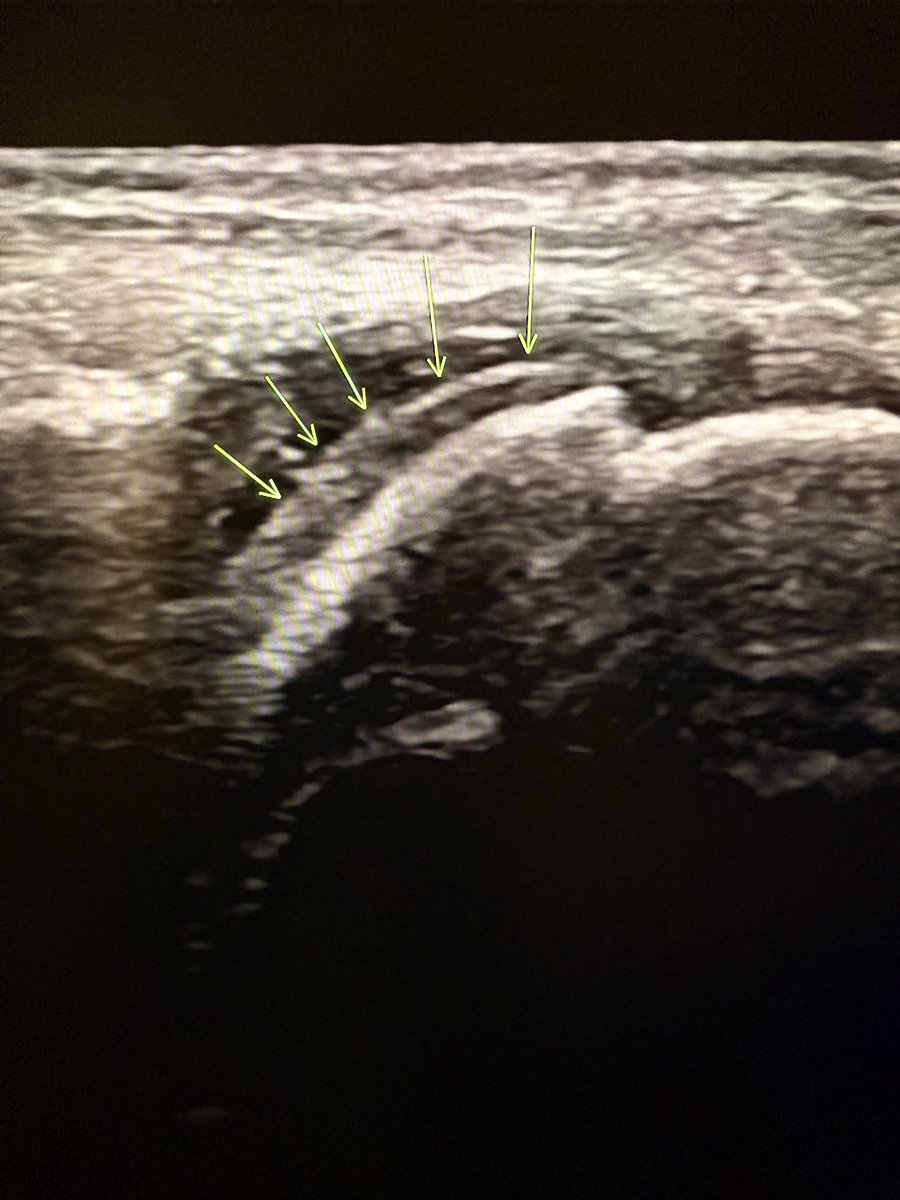

Double contour sign! It is a sonographic sign specific for gouty arthritis. Why does it occur? In gout, monosodium urate crystals deposit on the surface of the hyaline cartilage within the joint. This results in two distinct echogenic lines: 1.Deep line = normal

Double contour sign!

It is a sonographic sign specific for gouty arthritis.

Why does it occur?

In gout, monosodium urate crystals deposit on the surface of the hyaline cartilage within the joint.

This results in two distinct echogenic lines:

1.Deep line = normal